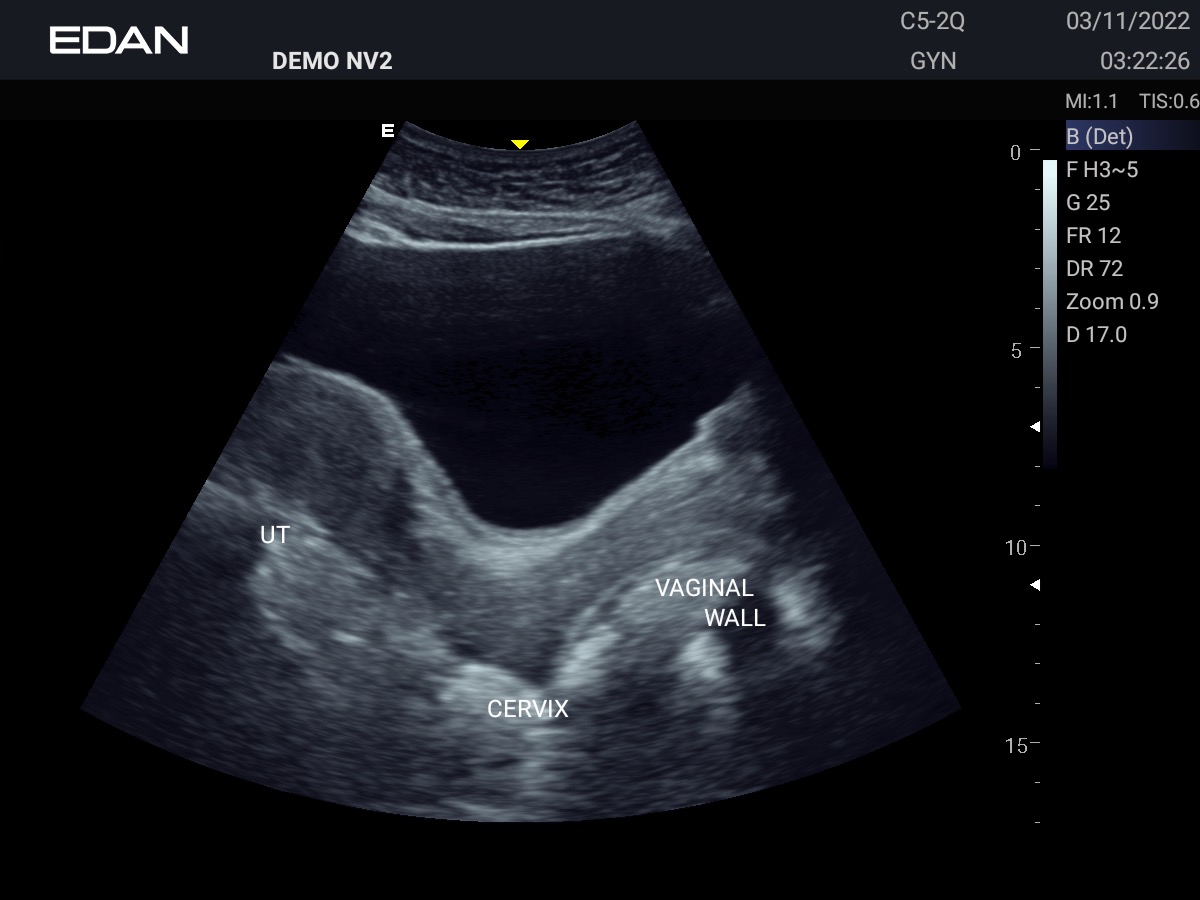

Clareza impressionante

Construído com a inovadora tecnologia Edan TAI e várias tecnologias de processamento de imagem, o Acclarix AX3 pode exibir perfeitamente a imagem de ultrassom em diferentes modos, auxiliando o ultrassonografista a fazer diagnósticos mais precisos.

- OB/GIN

Galeria de Imagens